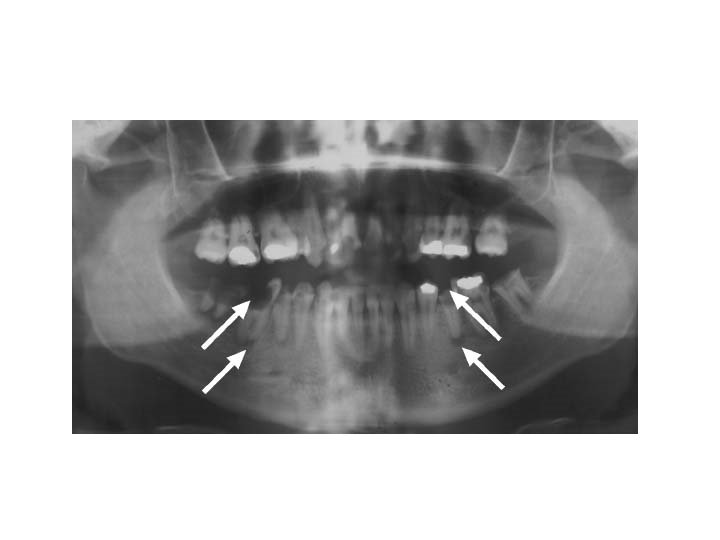

INDICES USED TO ASSESSMENT OF DENTAL CARIES 1. 2. 3. 4. 5. DMFT index DMFS index DEF index Stone’s index Caries severity index Diagnosis of caries 1. Identification of subsurface demineralization (inspection/ palpation, radiographs) 2. Bacterial testing (caries activity testing) 3. Assessment of environment conditions like salivary PH, flow and buffering